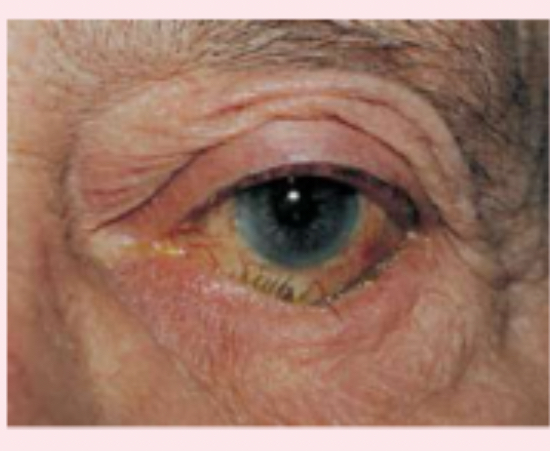

ectropion

outwardly turned lower lid